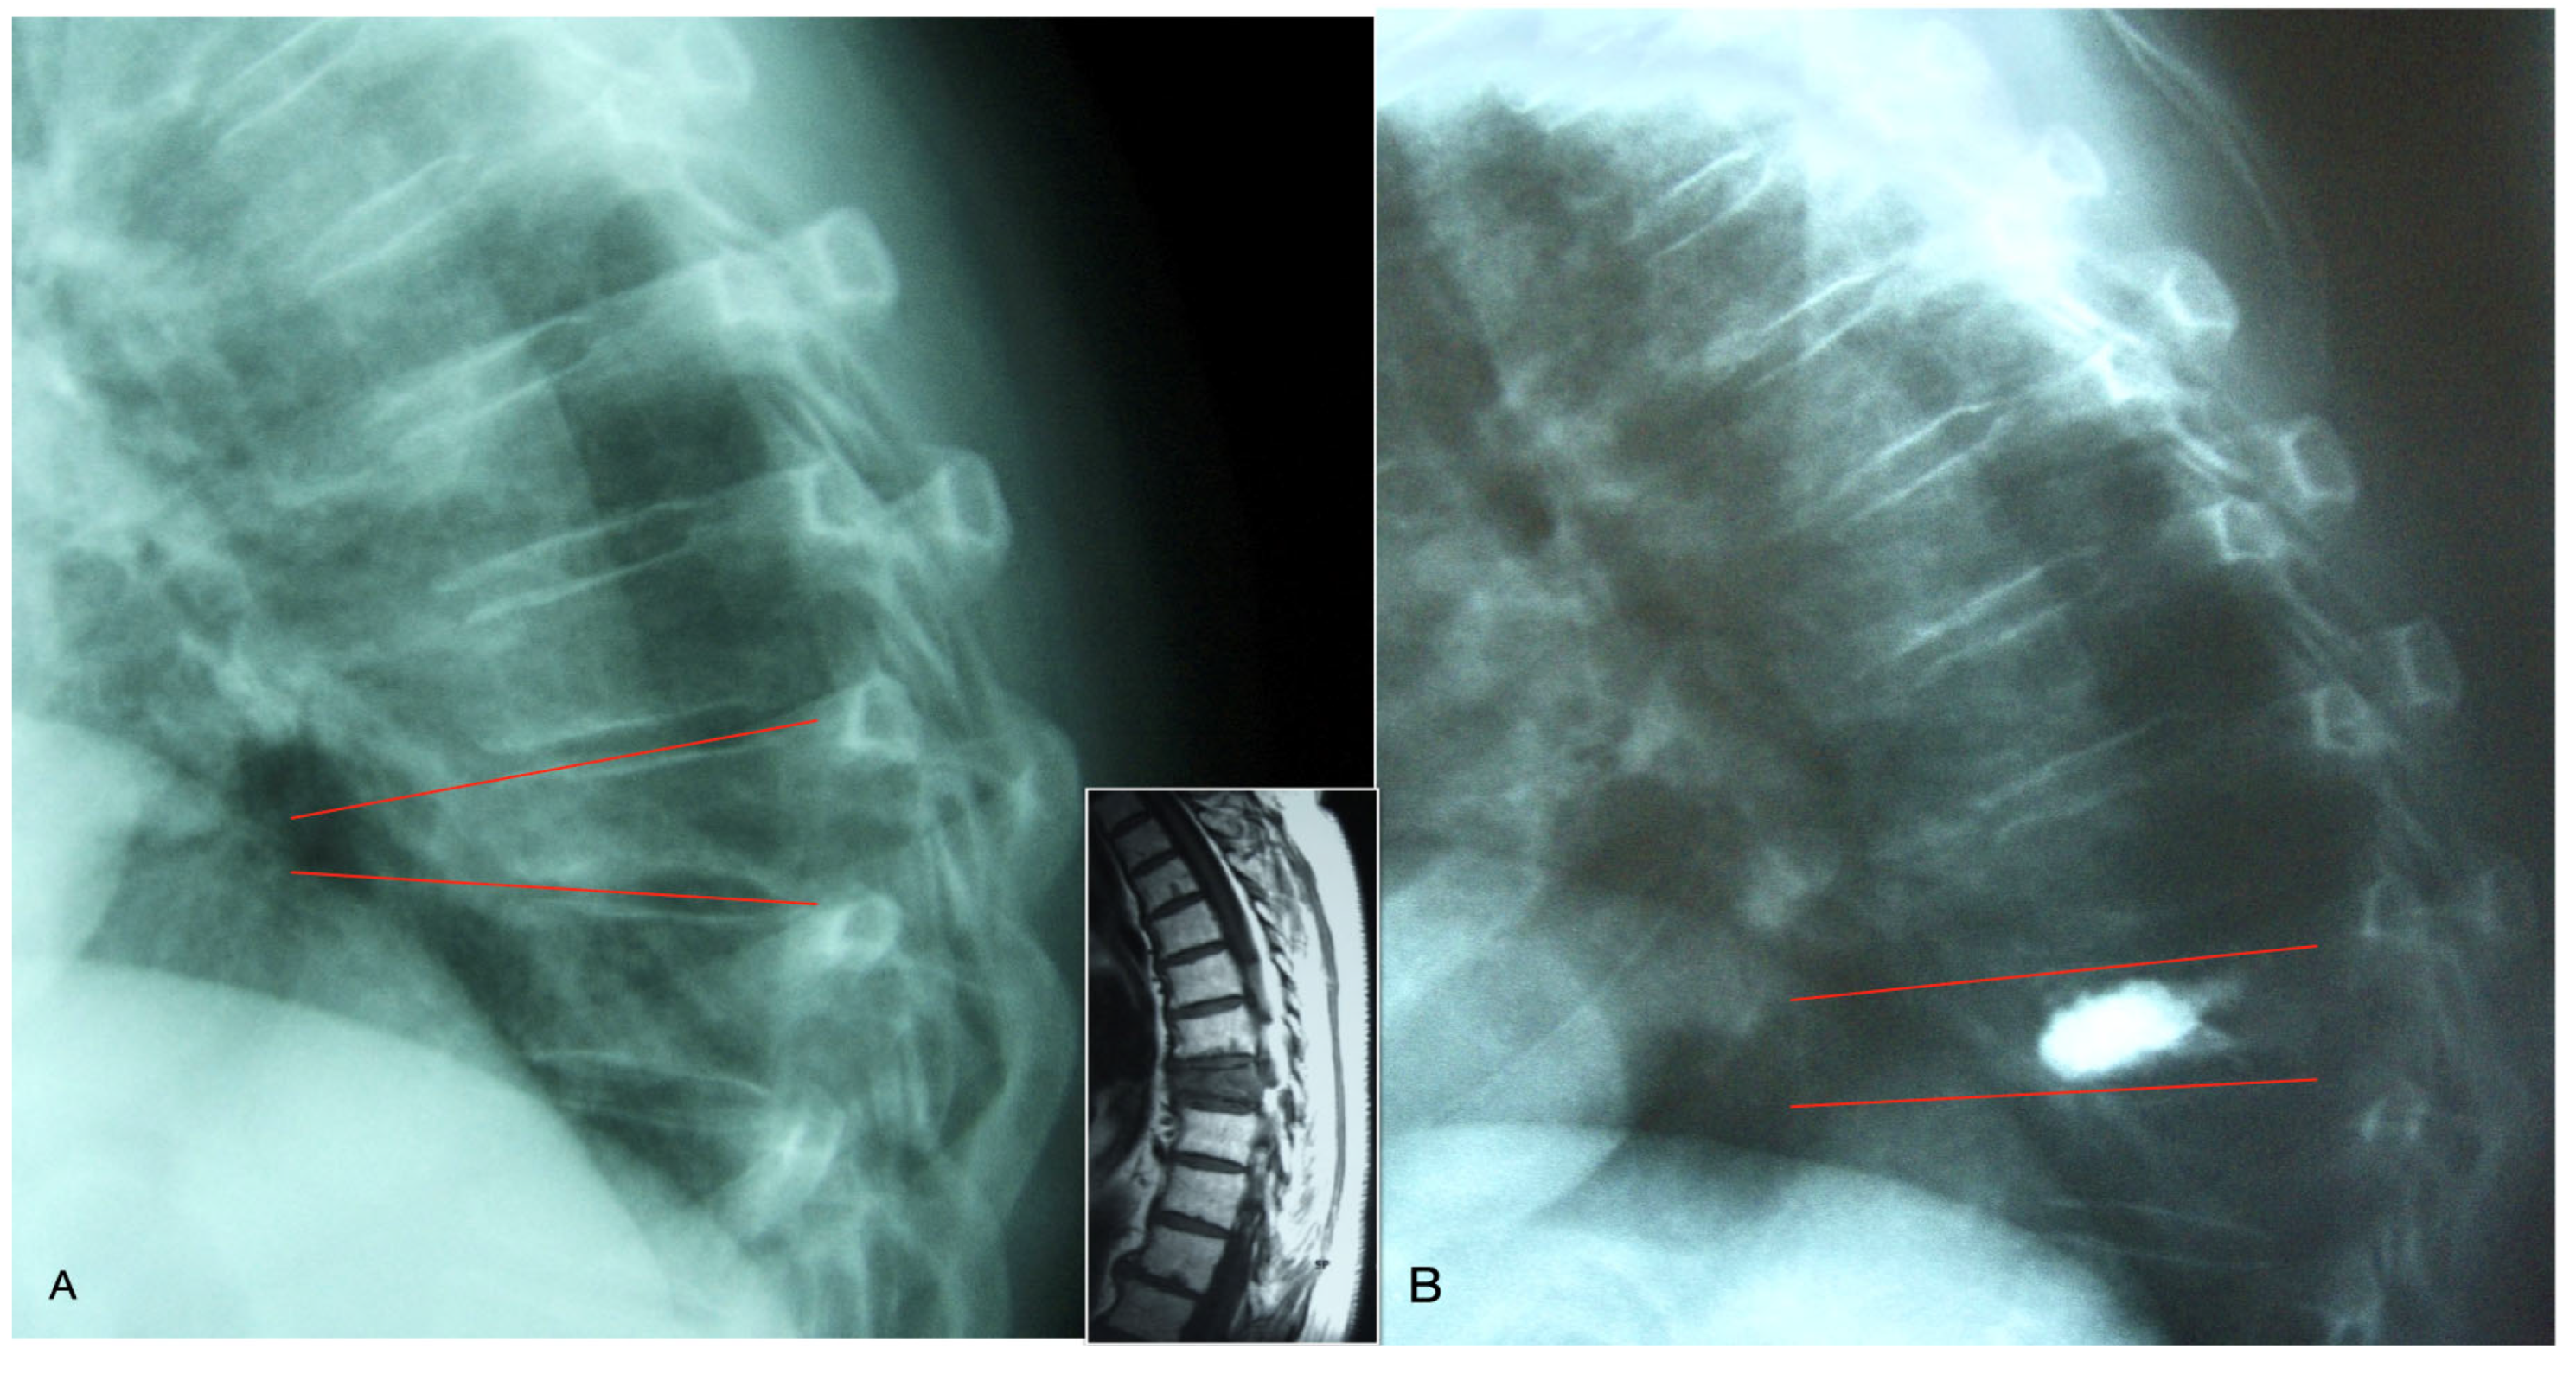

Unipedicular group: Patients were positioned similarly to the bipedicular group. After aseptic cleaning and covering the surgical field with a surgical drape, lidocaine was injected into the pedicle area and soft tissues under fluoroscopy control with a number 22 needle. Subsequently, the trocar was centrally placed in the vertebral body at an angle of 20° to 30° to the AP axis, using an extrapedicular approach under fluoroscopy. After inserting the guidewire, the cannula was introduced laterally to the posterior third of the vertebral body. The same balloon catheter was used in the unipedicular technique; the trocar was medialized 20–30 degrees in the anterior–posterior plane, and it was advanced to the anterior 2/3 of the vertebral body, aligning it with the central part of the body as much as possible (Figure 1). After the confirmation of the cannula by fluoroscopy, the balloon was inflated, and semi-solid bone cement was injected.

Figure 1. (A) The trocar was inserted in the extrapedicular site and medialized 20–30 degrees in the anterior–posterior plane, and it was advanced to posterior 1/3 of the vertebral body. (B) The working cannula was inserted through the guidewire. (C) It was advanced to the anterior 2/3 of the vertebral body, aligning it with the central part of the body as much as possible. (D) The balloon was inflated, and semi-solid bone cement was injected.